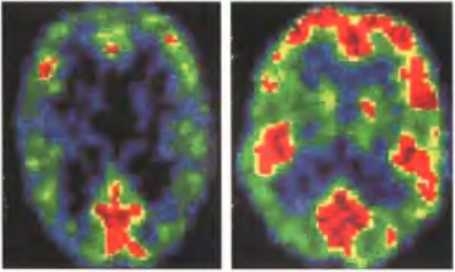

Существуют различия в работе мозга нормальных людей и преступников, совершивших насильственные преступления. Вверху показаны обобщенные результаты сканирования методом ПЭТ для 41 человека (39 мужчин, 2 женщины), обвинявшихся в убийстве и настаивавших на своей невиновности в связи с психическим заболеванием (слева), и для 41 здорового человека (справа). Результаты получены во время выполнения одинаковых заданий, связанных со зрительными стимулами. У убийц заметна меньшая активность лобных долей мозга, нужная для подавления таких эмоций, как ярость. Эта особенность наиболее отчетливо проявлялась у тех, кто совершил убийство в приступе гнева и не планировал его.

Результаты другой работы свидетельствуют о том, что у людей, совершающих насильственные преступления, в префронтальной коре в среднем на и % меньше серого вещества, чем у обычных людей. Кроме того, выяснилось, что у убийц наблюдаются повышенная активность отвечающих за эмоции участков правого полушария и пониженная интенсивность “межнейронного обмена” между полушариями. Это исследование проводил психолог Эдриан Рейн из Университета Южной Калифорнии. Он утверждает, что выявленные различия в активности лимбической системы между убийцами и обычными людьми указывают на то, что первые неспособны нормально испытывать страх и хуже, чем вторые, умеют прогнозировать долговременные последствия каких-либо действий.